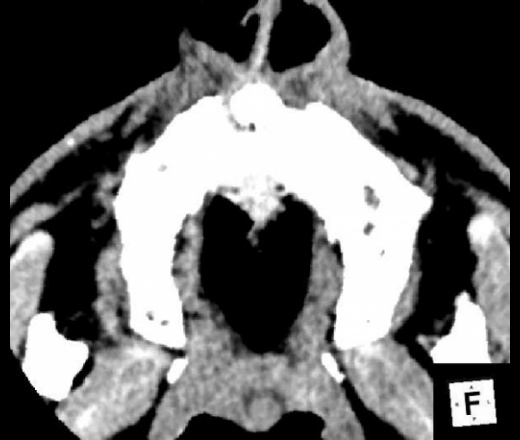

К делу подключились нейрохирурги, больной был экстренно прооперирован. Произведена КПТЧ, удаление субдуральной эмпиемы лобно-височно-теменной области справа, постановки дренажа под ТМО. Также вскрыты передние стенки обоих гайморовых пазух, произведена ревизия лобной пазухи, в пазухи заведены тампоны. По образному выражению нейрохирурга, при вскрытии ТМО получили: "Фонтан гноя". Снимки после операции:

Динамика отчетливо положительная, субдуральное гнойное содержимое практически полностью эвакуировано. Дислокация срединных структур уменьшилась. Определяется постоперационная пневмоцефалия.

Пациент провел 6 суток в реанимации. Состояние стабилизировалось. На 9е сутки пребывания очередное контрольное КТ:

В конвекситальных отделах правой теменной доли появилось несколько гиподенсных локальных зон, плотностью +15+20HU, с четкими неровными контурами; аналогичные зоны в полюсе правой лобной доли +19+25HU и в полюсе правой височной доли - формирующиеся кистозно-атрофические изменения? Сохраняется смещение срединных структур влево на 4мм. В зоне операции (КПТЧ) установлен дренаж, определяются немногочисленные пузырьки воздуха и пластинчатое субдуральное скопление патологического содержимого.

Переведен на ЛОР-отделение. Произведена левосторнняя этмоидотомия. Контрольное КТ головного мозга на 25е сутки пребывания.

Умеренная положительная динамика. Сохраняется зона формирующихся кистозно-атрофических изменений в лобной и височной долях справа плотностью +2+22HU. Срединные структуры смещены влево на 2 мм.